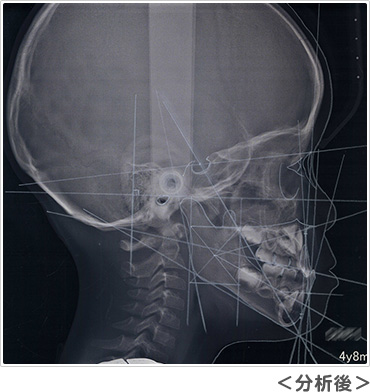

レントゲンは通常大きなレントゲンを2枚撮影します。パノラマレントゲンからは、おもに将来の永久歯の数が足りているか、永久歯の前歯はどのような形で生えてくるか、スペース不足はどのくらいか、などを予測します。セファロレントゲンからは、顔に対してアゴや歯並びがどのくらいの位置にあるのか、将来どのように成長する傾向があるのか、などを基準となる位置の角度を測って計測します。